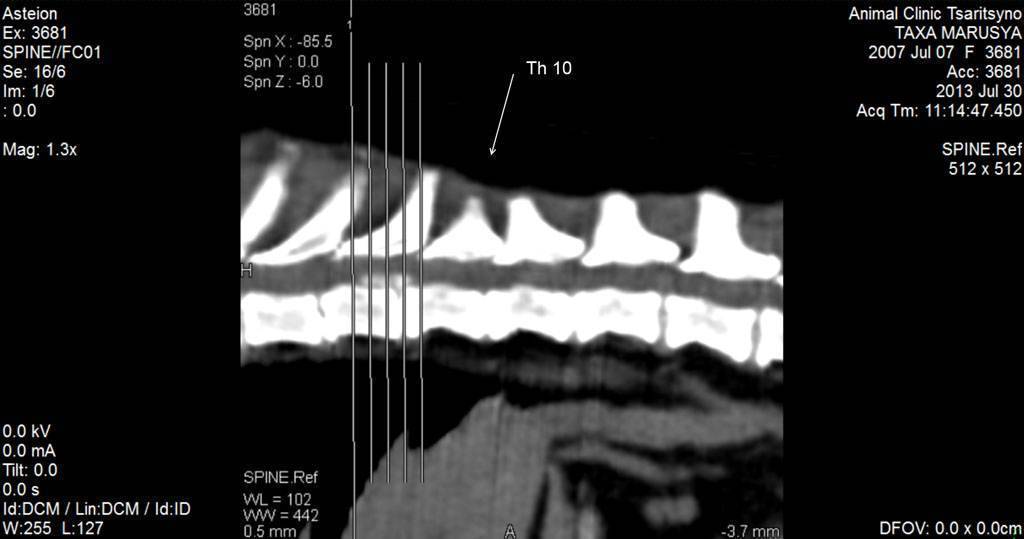

Рис. 1. КТ изображение в мягкотканном окне. Собака породы такса, самка, возраст 6 лет. Грыжа (выпадение) диска между 9 и 10 грудными позвонками. На фото в сагиттальной (серединной) проекции мы видим наличие массы белого цвета в просвете СМ (спинномозгового) канала. Это и есть грыжа диска. Данная грыжа является секвестрированной, т.е. элементы диска, смешавшись с кровью, вывалились в просвет СМ канала и мигрировали краниально (к голове) по СМ каналу. Анамнез болезни: вечером у собаки начали заплетаться задние конечности (парез), вялость, а утром собака не смогла встать (3 степень неврологического дефицита), недержание мочи. При клиническом осмотре выявлен неврологический дефицит 4 степени, т.е. у собаки отсутствовала поверхностная болевая чувствительность